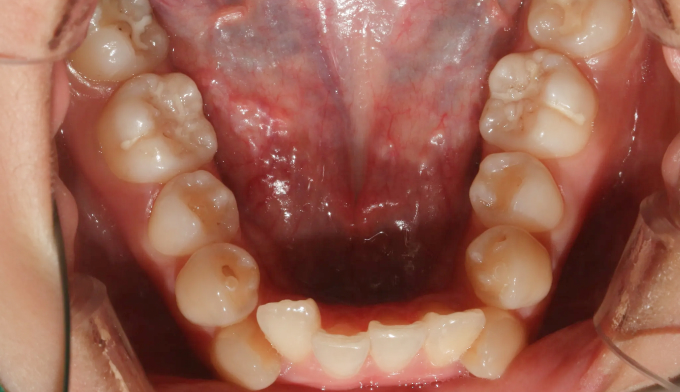

돌출입 정도는 약하지만, 공간이 매우 부족하여 덧니가 명확한 케이스 입니다.

치아 배열을 위한 공간이 많이 필요하기 때문에 발치를 통하여 공간을 먼저 확보하였습니다.

발치가 필요한 경우, 일반적으로 덧니인 송곳니보다는 작은어금니를 발치합니다. 가장 쓰임이 적고 덜 중요한 치아이기 때문입니다. 하지만 발치치아는 사람마다 그리고 케이스마다 달라집니다.

가지런한 치열을 갖기까지의 교정기간은 21개월 이었습니다.